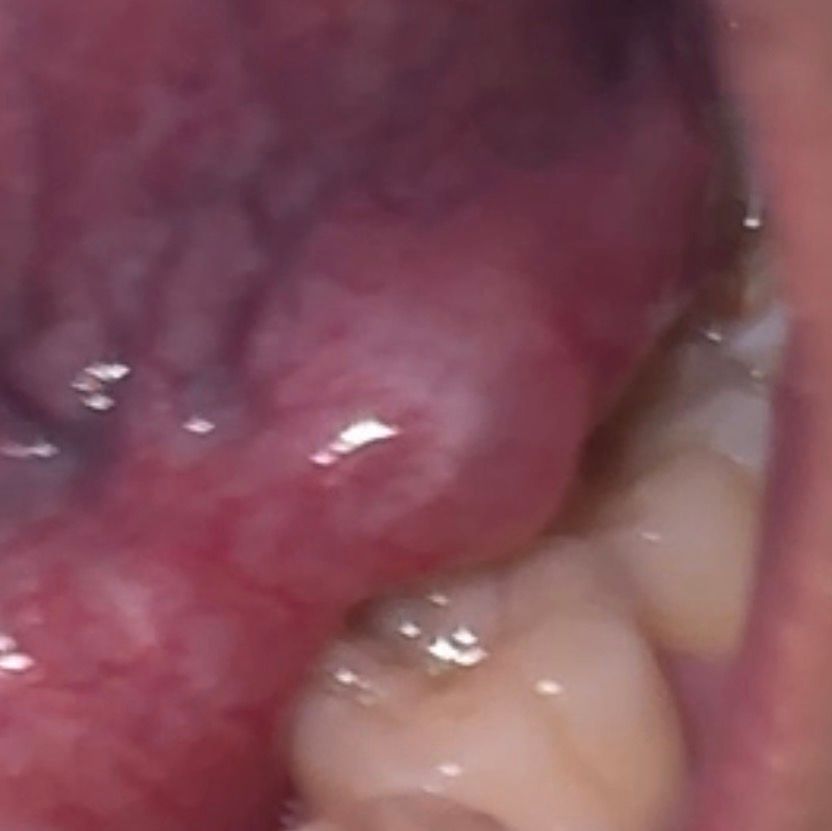

혀 밑에 볼록한게 느껴져서 봤더니 사진처럼 물집같은게 생겨있는데 뭔지 모르겠어요 약간 투명하고 만지면 잘 만져지지는 않는데 젤리처럼 약간 말랑거리는거 같아요 이게 뭔가요??

• 1번 째 사진

• 사진과 설명을 종합하면 혀 밑 점막에 생기는 점액낭종(타액낭종, 흔히 ranula라고 부르는 형태) 가능성이 가장 높습니다. 침샘관이 일시적으로 막히거나 미세 손상으로 침이 고이면서 투명하고 말랑한 물집처럼 보이는 병변이 생기는 기전입니다. 통증이 크지 않고 젤리처럼 만져지는 특징이 전형적입니다.